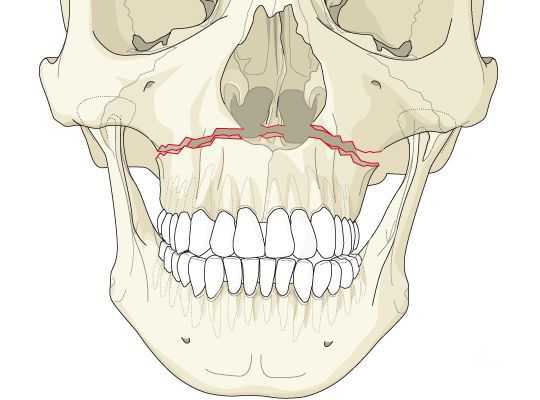

Чаще всего переломы классифицируют по Рене Ле Фору. Этот французский хирург систематизировал и описал формирующиеся повреждения костей средней зоны лица экспериментально: на головы свежих человеческих трупов он оказывал разные по направлению и силе воздействия по типу тупой травмы. Именно так и было обнаружено, что большинство линий переломов проходит по трём типам [1] :

- | тип — нижний, или горизонтальный тип, перелом Герена — Ле Фора. Перелом проходит над альвеолярным отростком и нёбным отростком через боковую и переднюю поверхности верхней челюсти, от крыловидных отростков основной кости к краю грушевидного отверстия.

- || тип — средний, или пирамидальный перелом, суборбитальный перелом. Линия перелома проходит через корень носа, внутреннюю стенку глазницы и далее — через нижнеглазничную щель кпереди по нижней стенке глазницы к месту альвеолярно-скулового контрфорса с переломом крыловидных отростков. Проще говоря, верхняя челюсть единым блоком "отсоединяется" от остальных костей средней зоны лица.

- ||| тип — верхний тип (поперечный, суббазальный, он же черепно-лицевое разъединение). Самый грозный вид перелома верхней челюсти, когда происходит отрыв верхней челюсти вместе со скуловыми костями от мозгового черепа. Как правило сочетается с тяжёлыми повреждениями головного мозга [3] .